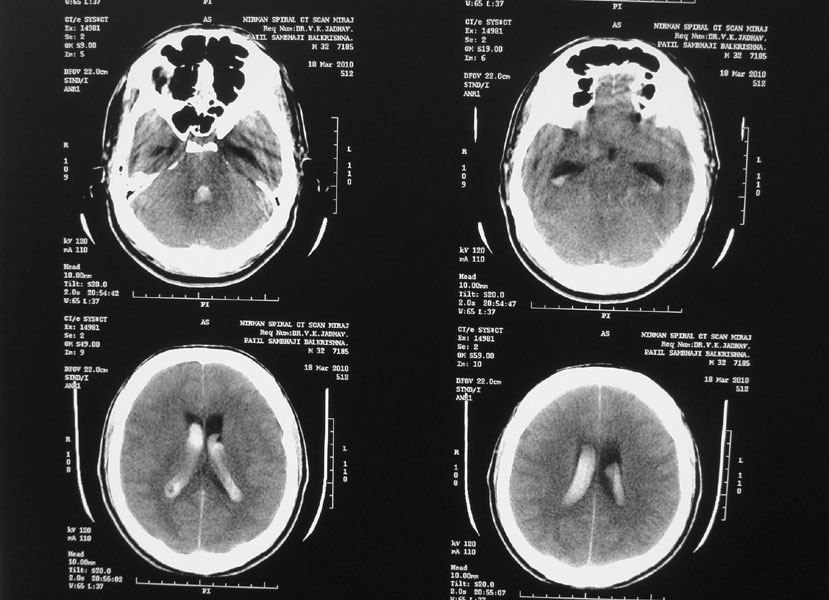

ICA Bifurcation Aneurysm

A 38-year-old-male was admitted with sudden onset of severe global headache and vomiting, followed by altereation in sensorium. CT brain showed subarachnoid and intraventricular hemorrhage (Fig 1). MRI brain revealed deep seated right sided thalamic hematoma due to ruptured internal carotid artery bifurcation aneurysm (Fig 2), confirmed by cerebral digital subtraction angiography (Fig 3). He underwent clipping of the aneurysm by transciliary supraorbital keyhole minicraniotomy (see video). Postoperative angiography showed complete occlusion of the aneurysm (Fig 4). When discharged ten days later, there was no neurological deficit (Fig 5).

Fig 1

(Fig 1)